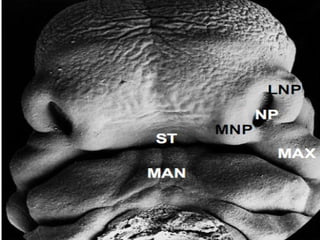

Formation of the face

Both the frontonasal process and the branchial

arches play a large

part in the formation

of the face and the

oral cavity.

The face derives from five prominences that surround the

stomodeum.

The prominences are:

• the single median frontonasal

prominence and

• the paired maxillary prominences

• and mandibular prominences;

A = Maxillary process

B = Mandibular process

C = Medial nasal process

D = Lateral nasal process